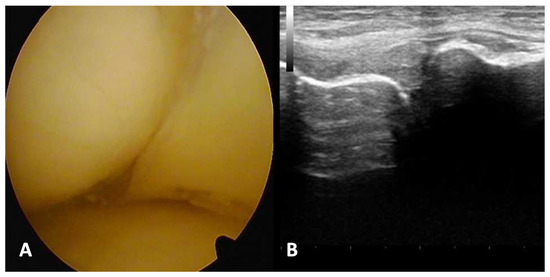

In part I of the experimental part of the study, ultrasonographic types of meniscal injuries were identified based on the analysis of morphological and ultrasonographic presentations of meniscal tears (Figure 1 and Figure 2). The following features of meniscal injuries as presented in ultrasound scans were identified and considered in the further part of the study: (a) the change in meniscal shape with concomitant degeneration of meniscal structure; (b) the change in the presentation of capsular attachment; (c) sharpening and degenerative lesions of the bony outlines of coronary ligament attachments; and (d) articular space stenosis.

Figure 1. First stage of experimental study, knee joint specimen arthrotomy. (A) Presentation of unremarkable lateral meniscus; (B) presentation of damaged lateral meniscus—radial type.

Figure 2. First stage of experimental study: ultrasound examination. (A) Presentation of unremarkable lateral meniscus; (B) presentation of damage of lateral meniscus—radial type.